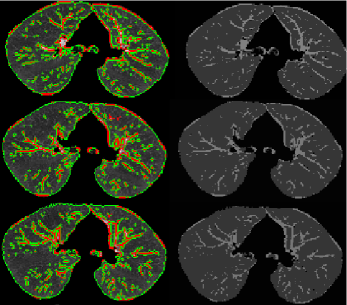

Elongation indicates the flatness of the shape. Compactness feature measures the similarity between shape of interest and a perfect ellipse. Fig. 3(c) and (d) show mean and Gaussian curvature maps from which all the other local shape features are extracted. Fig. 3(e) and (f) show Willmore energy map extracted from Fig. 3(a).

Based on the observation in training, TIB patterns most likely occur in the regions inside the lung with certain ranges (i.e, blue and yellow regions). This observation facilitates one practically useful fact in the algorithm that, in the feature extraction process, we only extract features if and only if at least “one” b-scale pattern exists in the local region as well as Willmore energy values of pixels lie in the interval observed from training. Moreover, considering the Willmore energy has a role as hard control on feature selection and computation, it is natural to investigate their ability to segment images. We present a segmentation framework in which every voxel is described by the proposed shape features. A multi-phase level set [6] is then applied to the resulting vectorial image and the results are shown in Fig. 3(g). First and second columns of the Fig. 3(g) show segmented structures and the output homogeneity maps showing segmented regions in different grey-level, respectively. Although segmentation of small airway structures and pathological patterns is not the particular aim of this study, the proposed shape features show promising results due to their discriminative power.

g